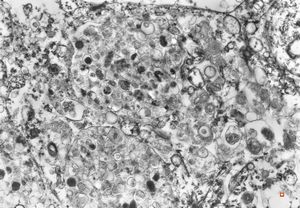

F,69y. | urinary bladder - malakoplakia